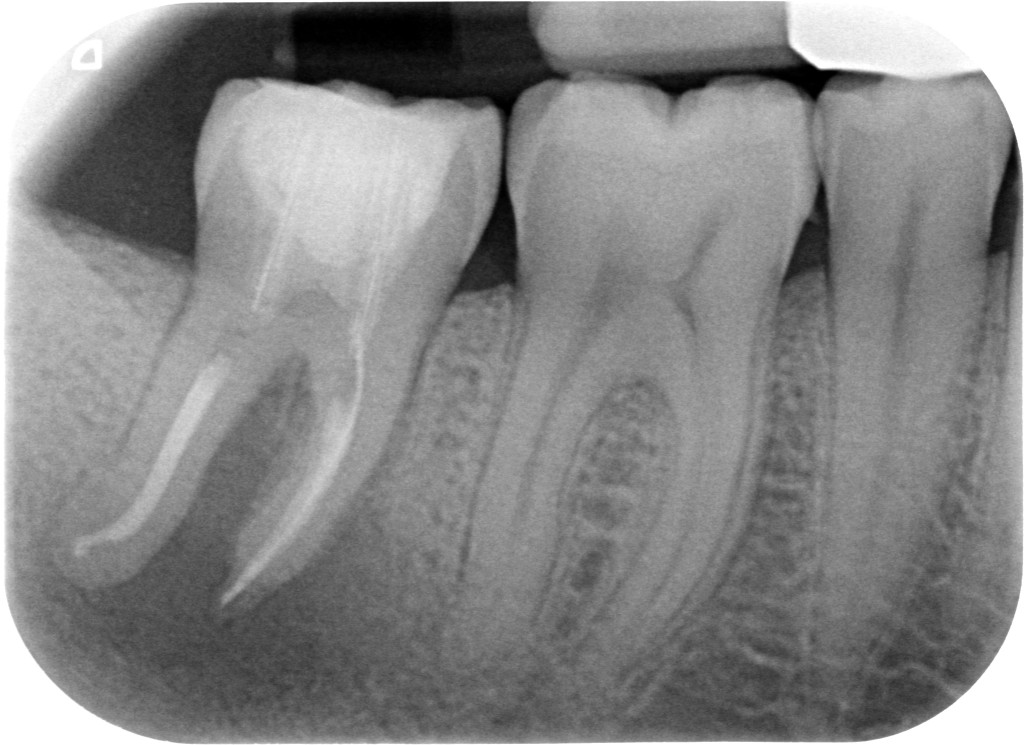

Come molti di voi, per me i primi molari inferiori avevano 3 o 4 canali, due mesiali e uno o due distali, mentre i secondi molari ne avevano più spesso 3, ogni tanto solo 2 e facevo attenzione alla eventuale presenza di un C-shaped canal.

Pur sapendo che esistevano molari con 5 canali alla fine mi accontentavo di trovare i classici canali.

Che ci potesse essere un canale mesiale-mediano lo sapevo ma alla fine non lo vedevo mai, nemmeno al microscopio, forse perché da anni lavoro su denti da ritrattare e non ero aiutato da eventuali sanguinamenti residui dopo la strumentazione dei canali “convenzionali”.

La scoperta che il canale mesiale-mediano deve essere cercato ed è spesso presente ha dato una soluzione a questi casi che mi capitano con una certa frequenza. Canali della radice mesiale del primo molare inferiore chiusi in apparenza bene con lesione. Il mio socio che si occupa quasi solo di chirurgia continuava a dirmi che poteva essere un problema di detersione, ma io a questo non ho mai creduto. Se un canale chiuso radiograficamente bene ha una lesione o è fratturato in verticale o manca un canale.